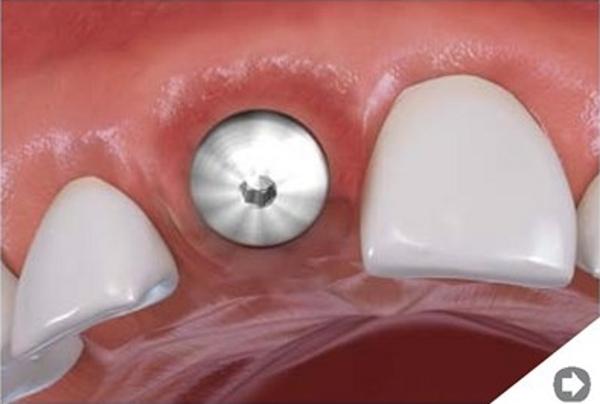

Sterowana regeneracja kości (GBR, Guided Bone Regeneration) wykorzystywana jest do odbudowy kości wyrostka zębodołowego w pożądanym wymiarze. Zabieg można wykonać podczas implantacji lub przed wprowadzeniem implantu, jako oddzielną procedurę. Uzyskuje się dzięki niemu poszerzenie lub podwyższenie wyrostka zębodołowego.

W implantologii regeneracji poddaje się kość wyrostka zębodołowego szczęki lub żuchwy, która uległa z różnych przyczyn zanikowi – jej niedostateczna ilość i jakość uniemożliwia wprowadzenie implantów. Po zakończeniu procesu sterowanej regeneracji, kość jest trwale zmieniona i często nie do odróżnienia od kości własnej.